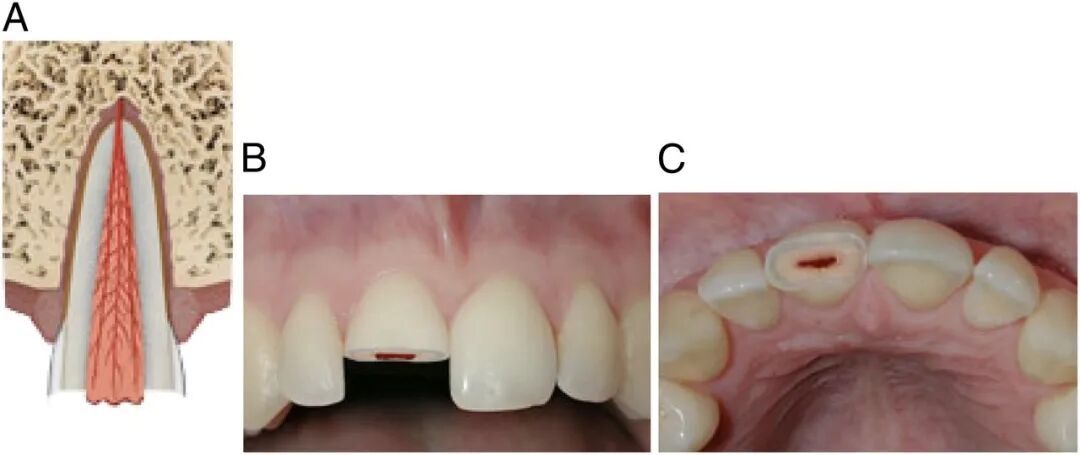

2、牙齿摔断

牙齿摔断依旧需要家长先找到掉的那半截牙,不过不用考虑保持细胞活性,所以不用泡牛奶了,找不到掉牙也没关系,尽快送医。

断牙治疗主要看断开的位置有没有暴露牙神经,分牙冠折断、牙根折断和冠根均折断等三种类型。

没有暴露牙神经,处理就比较简单。只需将牙釉质断面较锐利的地方磨光滑,不扎舌头即可。

也可以采用断冠再接的办法,把磕掉的那半截牙冠再粘回去。

如果牙齿断得比较靠近牙根,或者摔裂了,裂缝延伸到牙根,这些情况可能会伤到牙神经,处理起来复杂一些。

图源:AAP

为了防止牙神经感染,牙医通常采用一些材料,覆盖到这个露出神经的表面,然后再用材料把牙齿外形严密封闭。

如果牙齿磕断时间较长,露出的牙神经比较多,就采取牙髓切断术把受感染的这一部分牙神经去掉,把健康的牙髓保留下来,让牙根继续生长和发育。